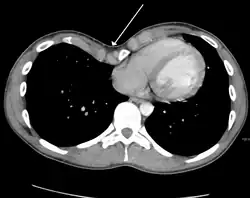

Physiologically, increased pressure in utero, rickets and increased traction on the sternum due to abnormalities of the diaphragm have been postulated as specific mechanisms.[12] Because the heart is located behind the sternum, and because individuals with pectus excavatum have been shown to have visible deformities of the heart seen both on radiological imaging and after autopsies, it has been hypothesized that there is impairment of the function of the cardiovascular system in individuals with pectus excavatum.

Many scales have been developed to determine the degree of deformity in the chest wall. Most of these are variants on the distance between the sternum and the spine. One such index is the Backer ratio which grades severity of deformity based on the ratio between the diameter of the vertebral body nearest to xiphosternal junction and the distance between the xiphosternal junction and the nearest vertebral body.[20] More recently the Haller index has been used based on CT scan measurements. An index over 3.25 is often defined as severe.[21] The Haller index is the ratio between the horizontal distance of the inside of the ribcage and the shortest distance between the vertebrae and sternum.[22]

Chest x-rays are also useful in the diagnosis. The chest x-ray in pectus excavatum can show an opacity in the right lung area that can be mistaken for an infiltrate (such as that seen with pneumonia).[23] Some studies also suggest that the Haller index can be calculated based on chest x-ray as opposed to CT scanning in individuals who have no limitation in their function.[24]